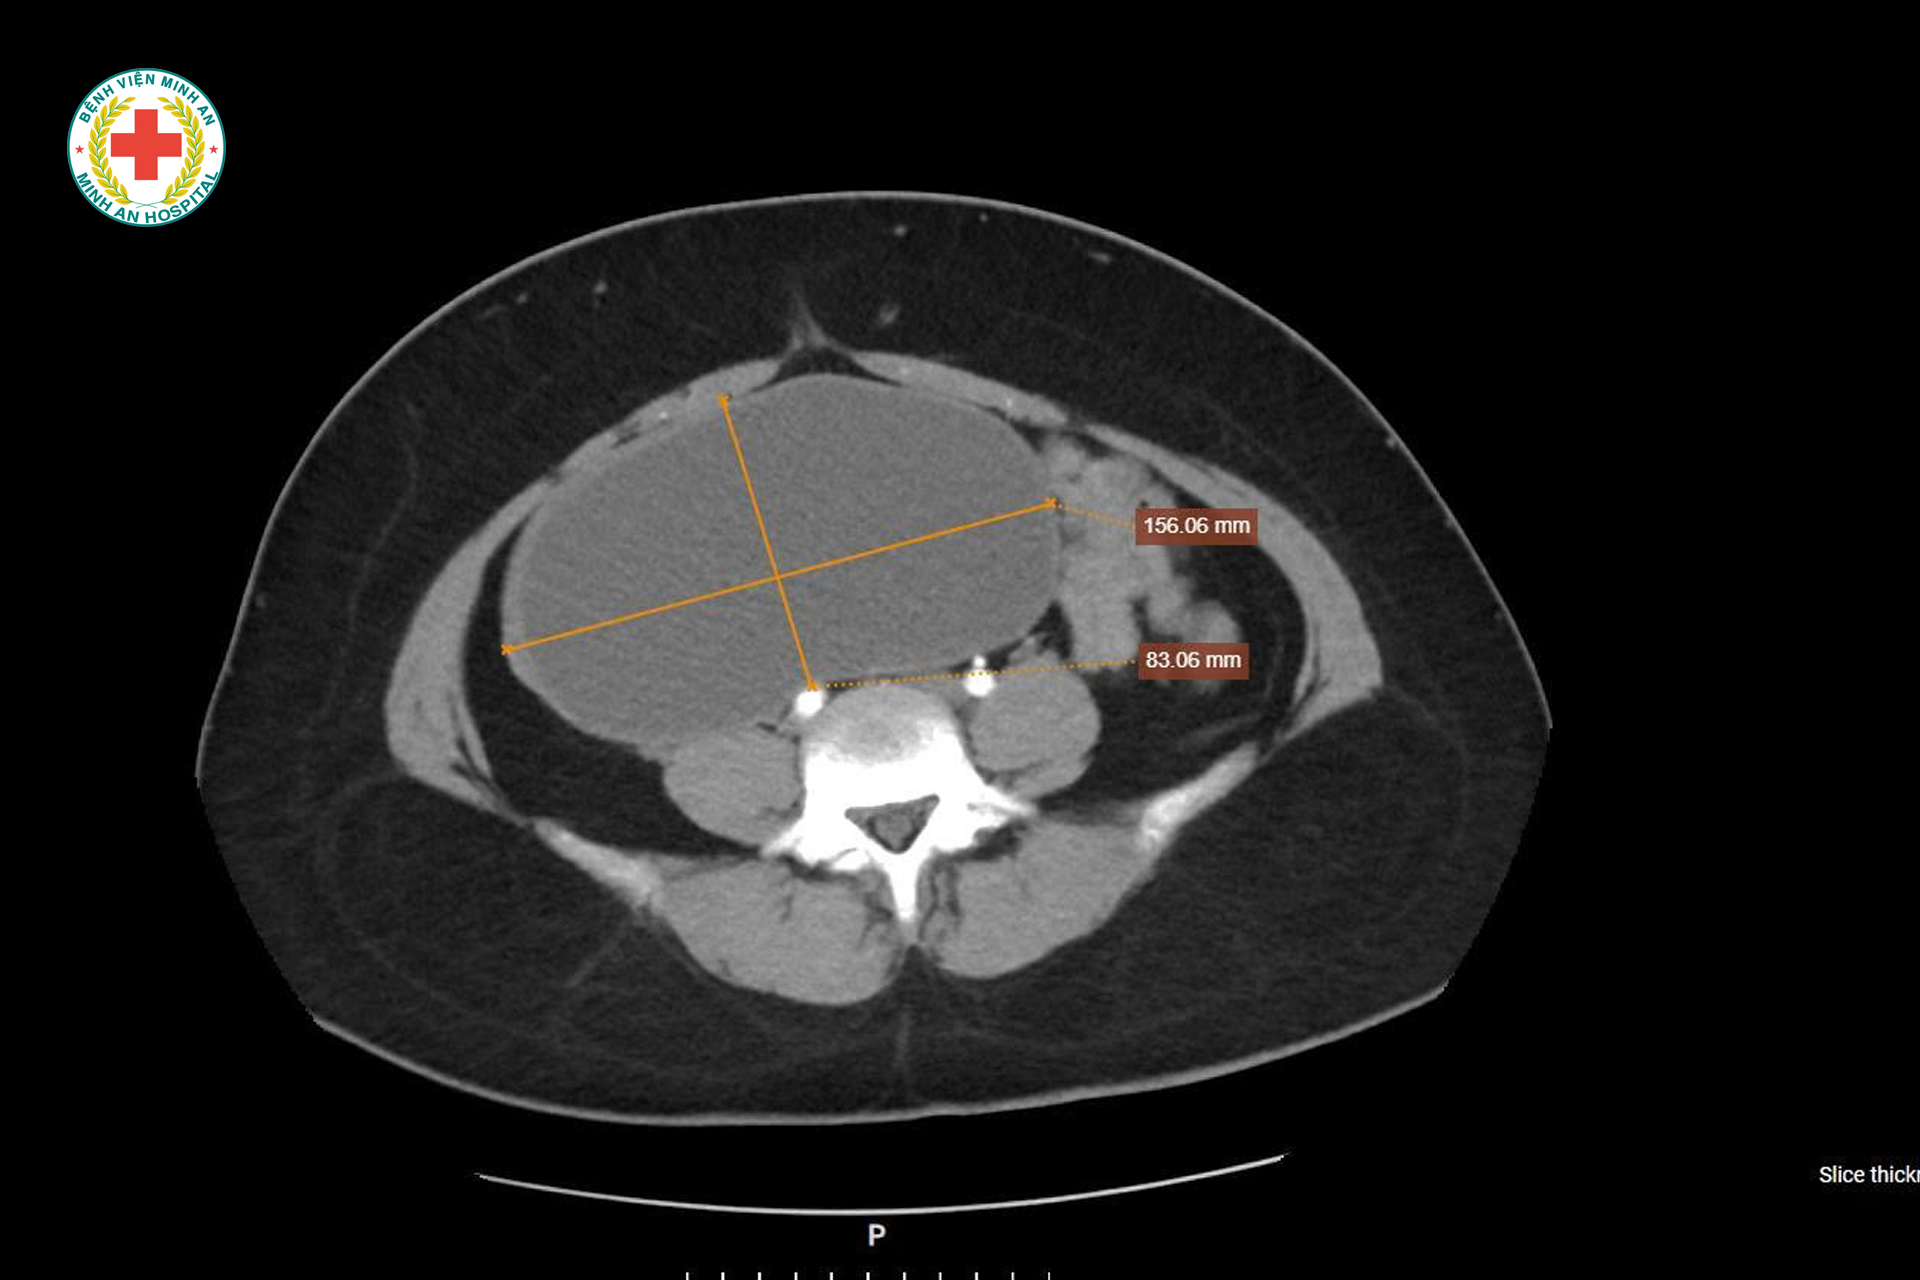

🔴 U NANG BUỒNG TRỨNG “KHỔNG LỒ” Ở CÔ GÁI 22 TUỔI – PHÁT HIỆN TÌNH CỜ, XỬ TRÍ KỊP THỜI, BẢO TỒN KHẢ NĂNG SINH SẢN

Khoa Sản – BVĐK Minh An vừa tiếp nhận tiếp nhận một trường hợp đặc biệt: U nang buồng trứng kích thước rất lớn, tương đương thai khoảng 20 tuần tuổi, người bệnh gần như không có triệu chứng rõ ràng, chỉ xuất hiện ra máu bất thường ngoài chu kỳ. Điều đáng chú ý là bênh nhân mới 22t, chưa từng sinh nở.